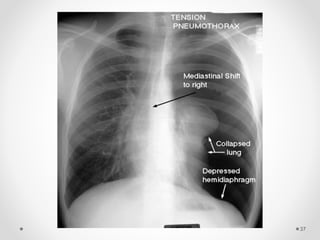

Tension pneumothorax

• It is life threatening condition.

• The pleural pressure is more than the atmospheric

pressure.

Radiological manifestations of large pneumothorax

• Mediastinal shift,

• Flattening of the hemidiaphragm &

• Lung collapse.

Associated with clinical manifestations of rapidly

progressive breathlessness and circulatory

collapse (tachycardia, hypotension & sweating).

It is more common with

• Positive pressure ventilation &

• Traumatic pneumothorax.